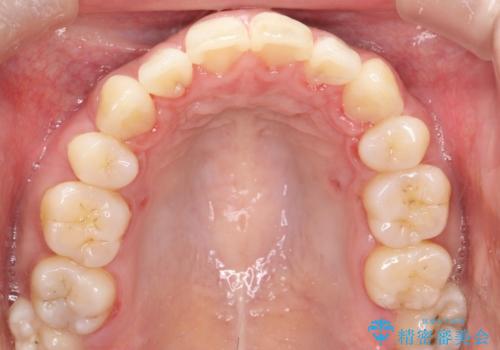

上顎の前から4番目の歯を両側抜歯して、上下裏側の装置で前歯を引っ込める計画としました。

裏側からの矯正であったため、表側に比べて少し治療期間を要しました。

目立たずに矯正治療を終えることができ、満足していただけました。